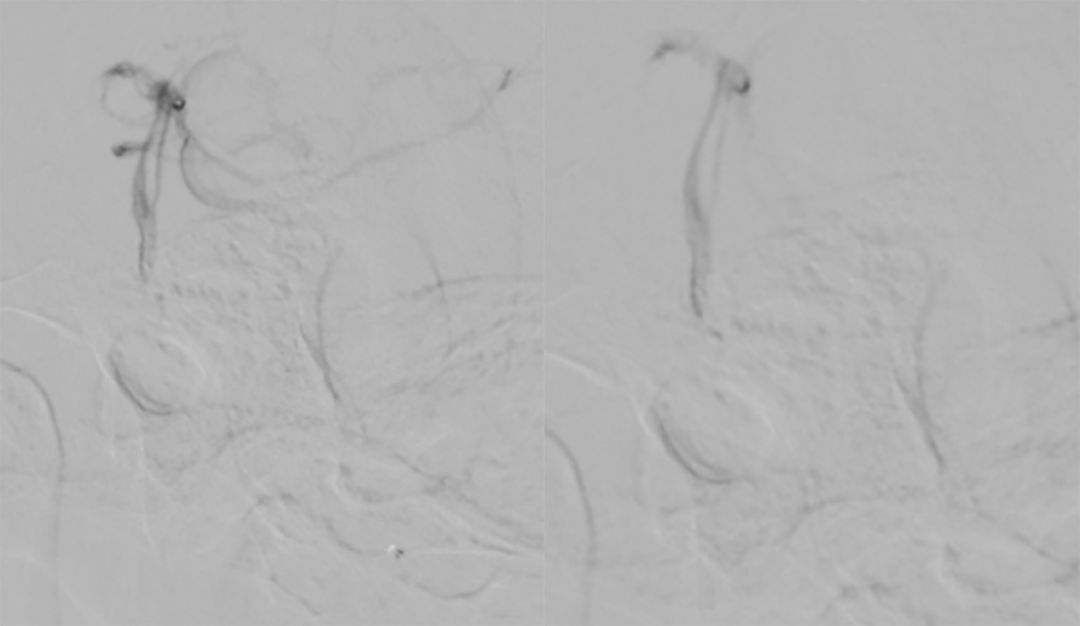

6. 多个投射角度辅助下,将数枚弹簧圈枚植入动脉瘤内(图12)。

图12

7. 术后造影显示动脉瘤完全栓塞,载瘤动脉通畅(图13)。

图13